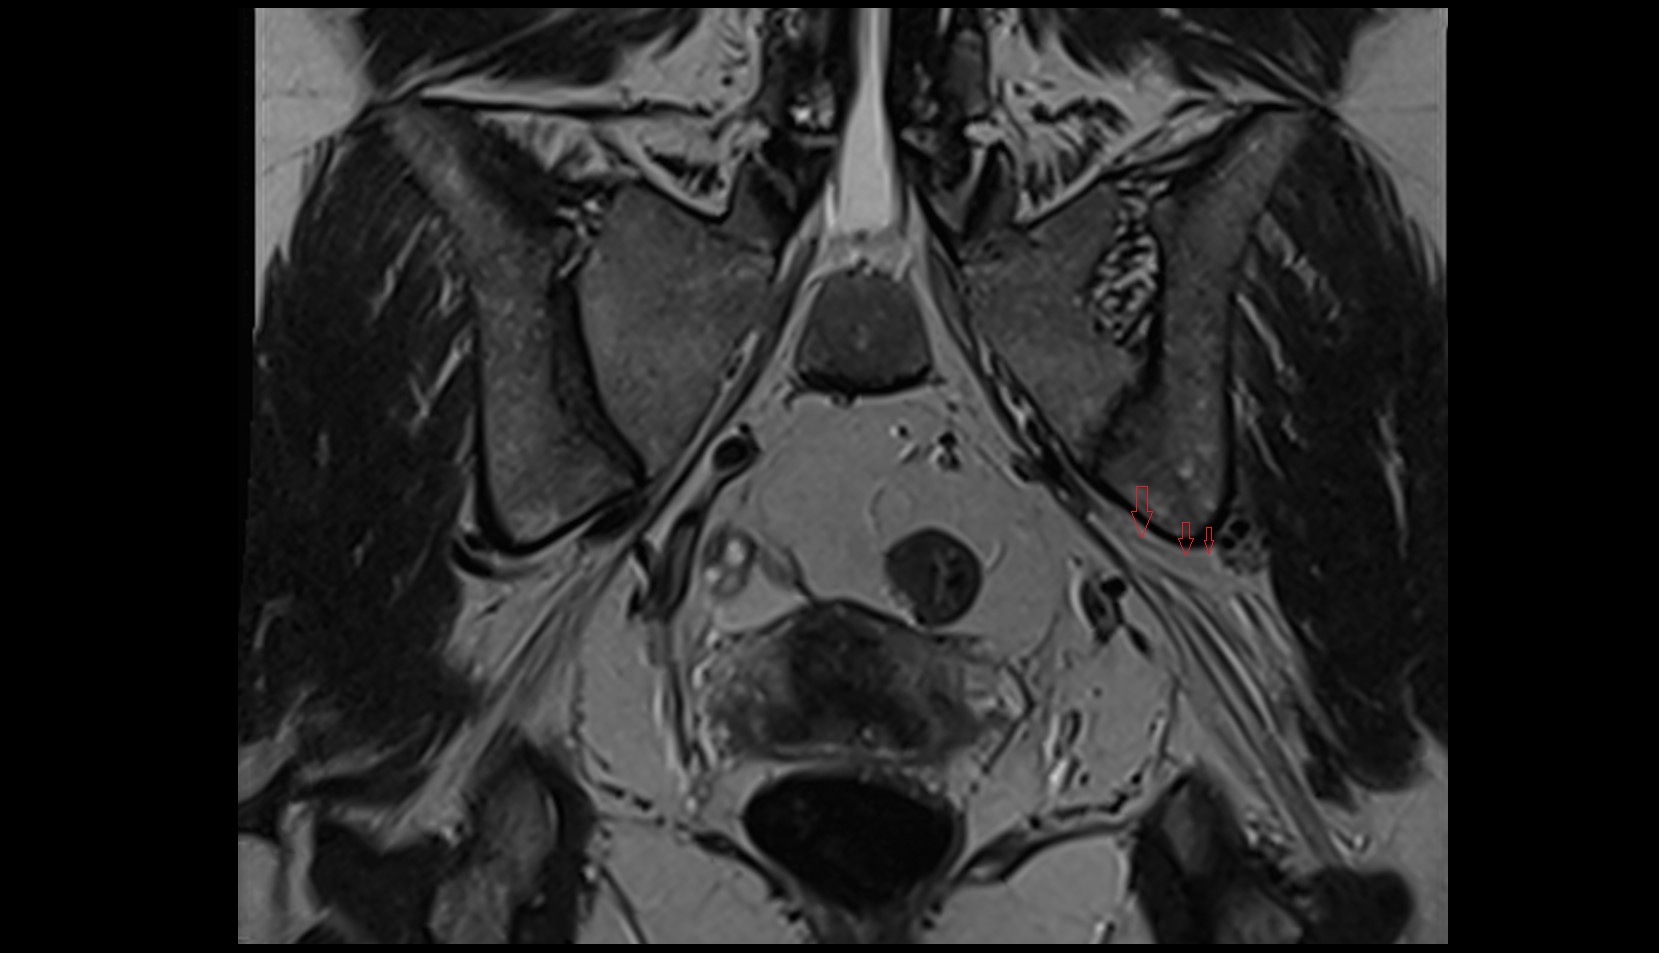

- Temporomandibular joint

- Mandibular condyle

- Mandibular fossa

- Articular disc of temporomandibular joint

- Articular eminence